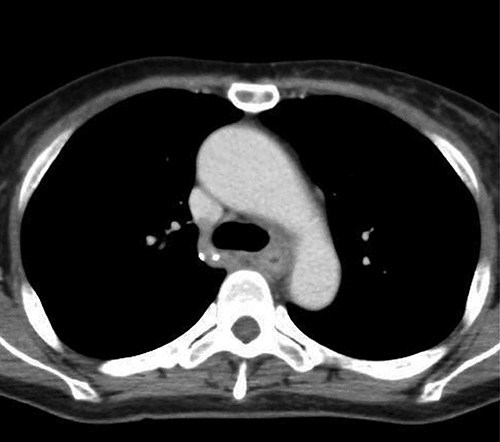

Preoperative computed tomography (CT) and barium meal studies were performed. The CT findings showed circumferential wall thickening with infiltrative change at the middle of the intrathoracic esophagus, with luminal dilation of the oral side of the stenotic esophagus (Figs 2, 3). The barium meal study showed no abnormal findings in the stomach (Fig. 4). Thoracoscopic esophagectomy was performed with the patient in the semi-prone position, followed by esophageal reconstruction using a gastric tube with the patient in the supine position. The operation was started with bilateral lung ventilation using a single-lumen endotracheal tube. A four-port thoracoscopic technique was used as follows: an observation port with a 10-mm scope was placed at the ninth intercostal space at the line of the inferior scapular angle, and two 5-mm ports and one 12-mm port for the intrathoracic procedures were placed at the third, fifth and seventh intercostal spaces, respectively, at the posterior axillary line (Fig. 5). Pneumothorax was created using 10 mmHg of CO2 to deflate the lung to achieve a better operative field. The pleura and connective tissue around the thoracic esophagus showed severe inflammatory and fibrotic changes. In particular, the middle thoracic esophagus was strongly adherent to the arch of the azygos vein and the tracheal bifurcation.

CT images showing a horizontal section of the esophagus; CT image shows circumferential wall thickening with infiltrative changes in the middle part of the thoracic esophagus.